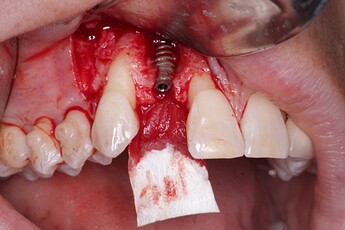

Pic 4

osseoseal-4

An implant was placed in site #7 with an existing buccal bone defect (Pictures 1 & 2). Prior to placing the bone graft over the implant, the membrane is measured and trimmed and tucked under the palatal flap trying to avoid wetting the entire membrane (Picture 3). The particulate bone graft (DALI Classic Cortical Cancellous Mix) is placed over the implant surface to restore the defect (Picture 4). The membrane is folded over the crest and onto and slightly beyond the particulate bone graft while slowly dropping saline onto the membrane (Picture 5). This enables the membrane to contour and drape over the graft and “seal” the graft off from the surrounding soft tissue (Picture 6 and 7). Sutures are then used to achieve primary closure over the GBR site (Picture 8).